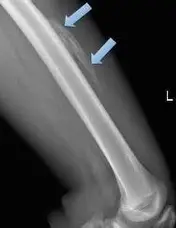

Patellar Fracture

Knee Fracture